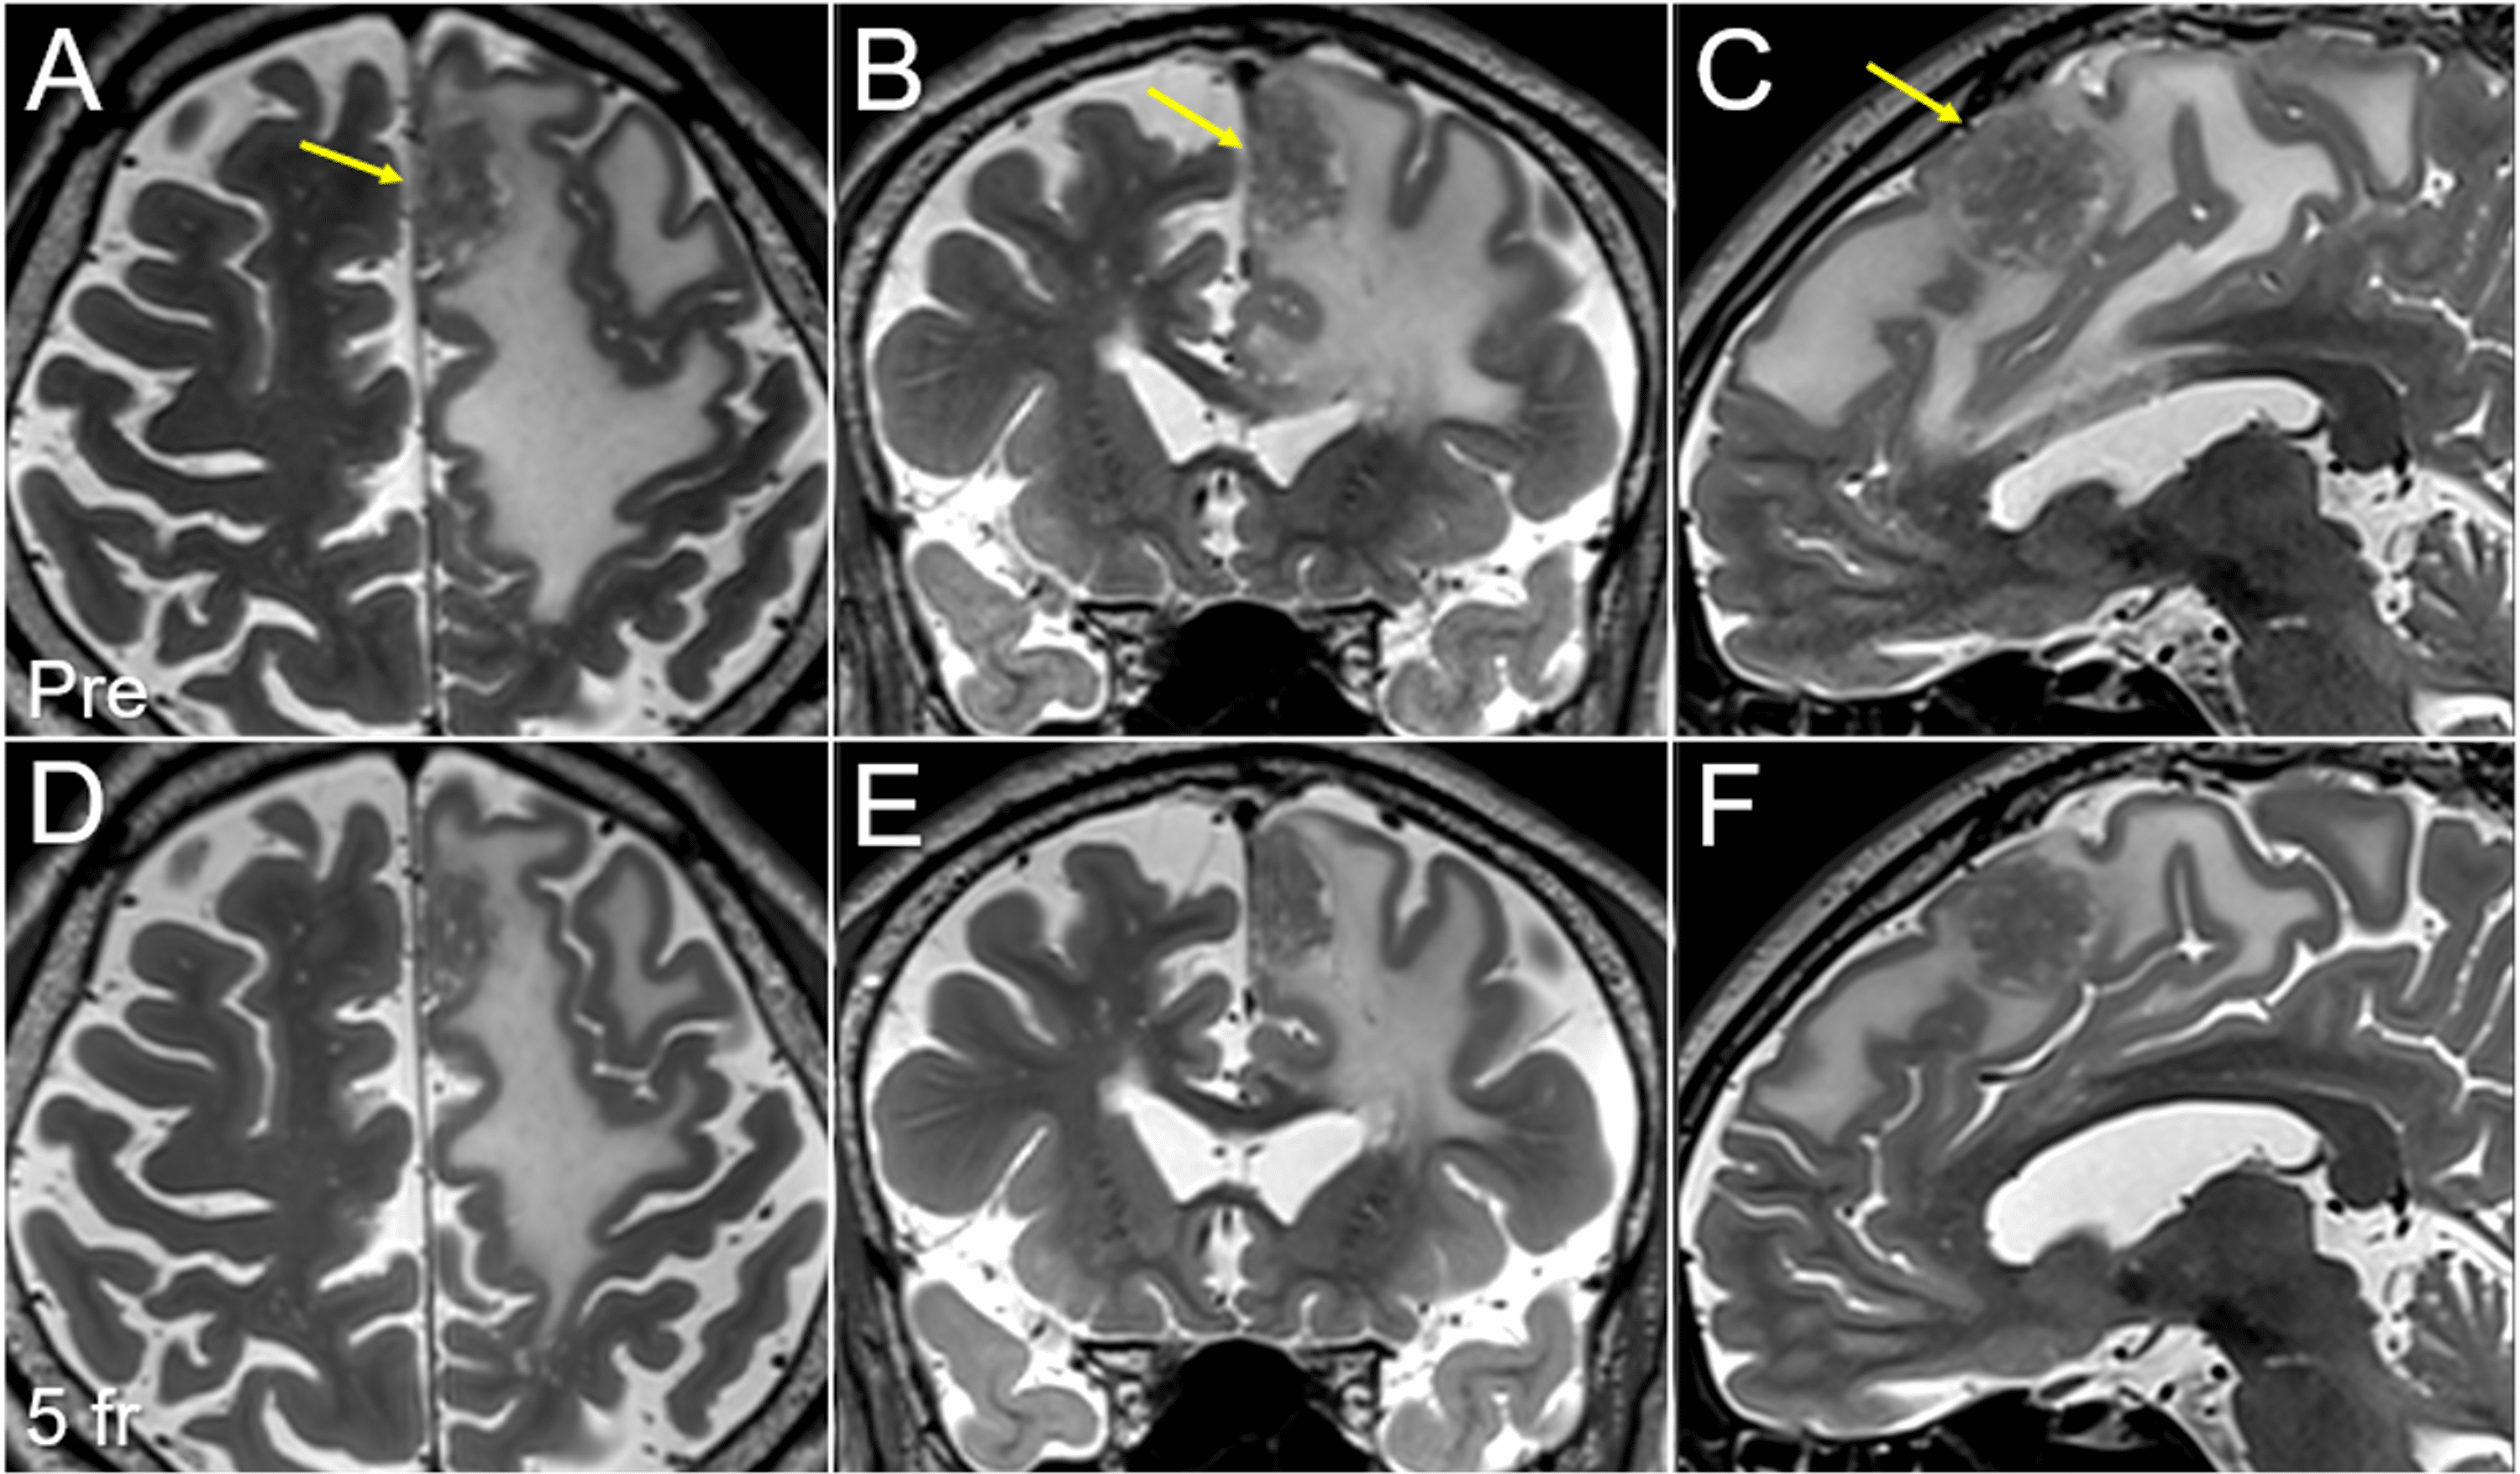

Frontiers A Multicenter Retrospective Study of Frameless Robotic Radiosurgery Protons Web stereotactic radiosurgery (srs) was conceived by a team of neurosurgeons and physicists in sweden. Web there are numerous advantages of protons over photons, so it is important to understand limitations with further studies. Web despite requiring specialized facilities for its generation and manipulation, proton radiation offers superior dose conformality relative. Part i deals with the relevant physics and planning. Radiosurgery Protons.